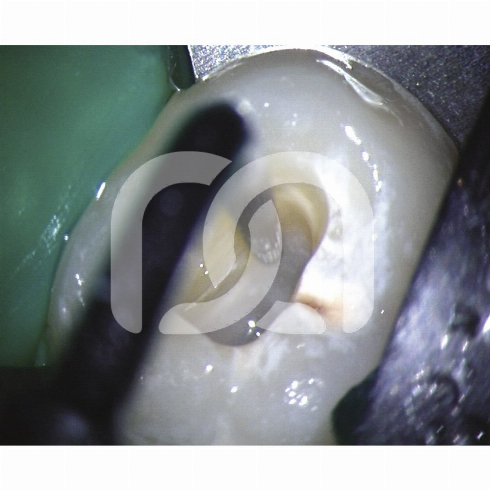

Insertsà ultrasons pour la finition de la cavité d'accès et la localisation des entrées canalaires.- Un insert endodontique Une indication clinique.- Start-X N° 1 : Finition des parois de la cavité d'accès.- Start-X N° 2 : Localisation du canal du 2ème canal racine mésio-vestibulaire.- Start-XN° 3 : Recherche et ouverture des canaux calcifiés.- Start-X N° 4 : Retrait des tenons métalliques.- Start-X N° 5 : Mise en forme de l'anatomie du plancher pulpaire. Caractéristiques - Partie active micro-fraisée : efficacité de coupe associée à une finition parfaite.- Port dirrigation : refroidit linsert et évite l'échauffement de la dent traitée, en particulier pour le descellement de tenon nécessitant une puissance élevée. Avantages - Une grande précision de travail.- Un gain de temps.- Excellente résistance à la fracture.